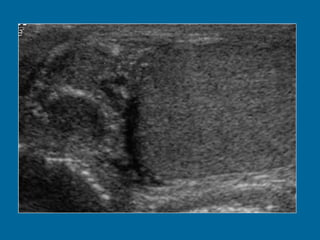

Tumor del seno endodermico mass.  (a)  Longitudinal US scan of the left hemiscrotum shows a solid tumor  (T)  replacing the entire testis. The cystic areas (arrowheads) represent tumor necrosis.

Tumor del senoendodermico mass. (a) Longitudinal US scan of the left hemiscrotum shows a solid tumor (T) replacing the entire testis. The cystic areas (arrowheads) represent tumor necrosis.